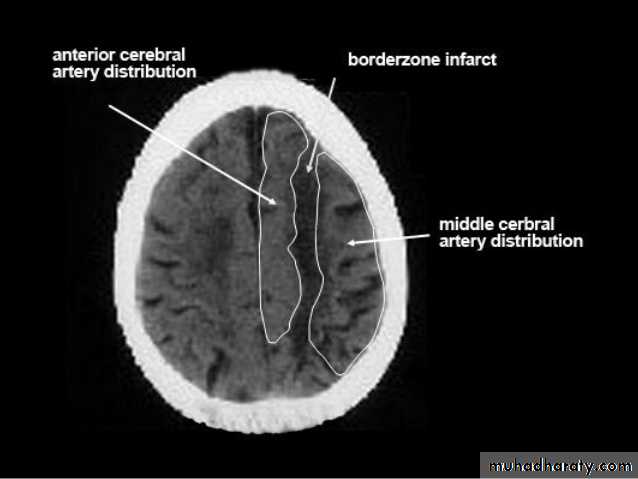

• Role of CT and MR in patients with stroke• Early CT and MR signs of infarction